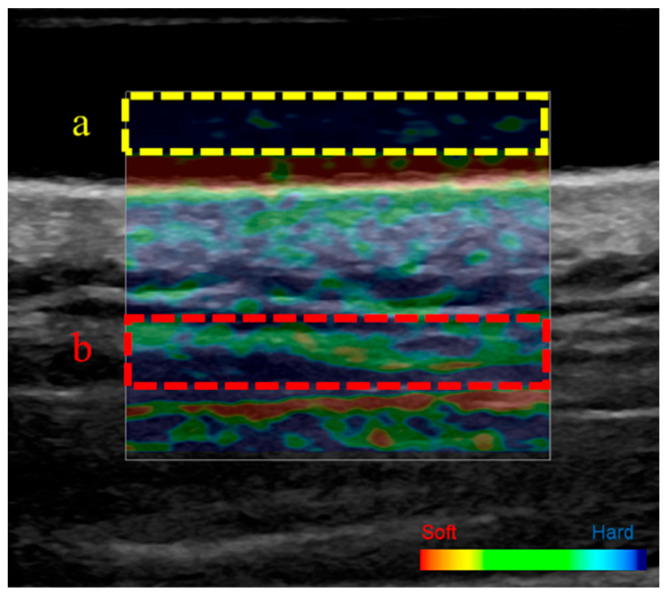

Methods: Eighteen healthy adults in their 20s (median age ± standard error: 21.0 ± 4.9 years) and eight healthy adults in their 40s (age: 43.0 ± 15.2 years) were included. Intraocular pressure (IOP); systolic, diastolic, and mean blood pressure (BP); heart rate (HR); ocular perfusion pressure (OPP); and salivary alpha-amylase (sAA) activity-as an indicator of autonomic nervous system function-were measured at baseline and after trapezius muscle self-stretching. Upper trapezius muscle stiffness was assessed using ultrasound strain elastography, whereas choroidal circulation was evaluated using laser speckle flowgraphy to determine the mean blur rate (MBR), a relative measure of macular blood flow velocity.